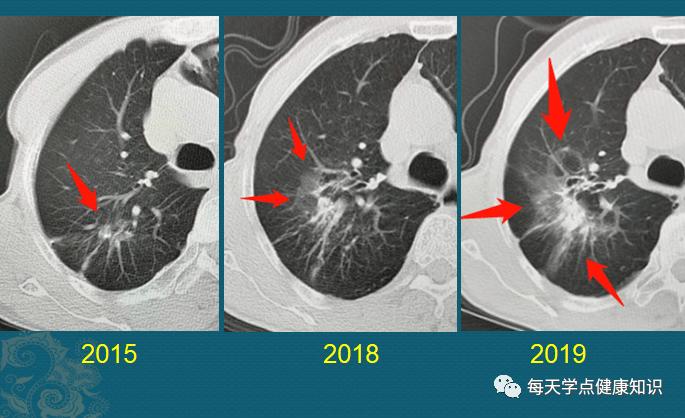

肺结节是怎么长出来的?医生用ct片详解,有2种可能是肺癌

ct示两肺多发结节(isobe t, et al. intern med. 2019)

肺磨玻璃结节的ct诊断